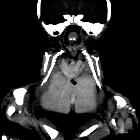

Radiographic assessment

Antenatal ultrasound

Thus identification of a dividing membrane or two placentas excludes the diagnosis. Definitive sonographic features will depend on the type of fusion.